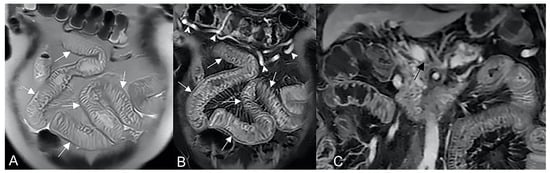

To assess the wall thickness, a good bowel distention is required (Figure 5A). Depending on the size, wall thickening should be subdivided as mild (3–5 mm), moderate (>5–9 mm), and severe (≥10 mm) [5]. However, asymmetric mass-like bowel wall thickening greater than 15 mm is atypical for Crohn’s disease, and cancer should be suspected. Intramural edema (Figure 5C) is typically investigated in fat-suppressed T2-weighted images where it appears as hyperintense intramural bowel. Ulcerations are consistent with a defect confined to the bowel wall, containing air or enteric intraluminal contrast that is focused in the inflamed bowel wall without extraluminal spreading [5,6]. The affected intestinal loops can present sacculation or pseudodiverticular extroversions of the antimesenteric side due to acute or chronic mesenteric border inflammation [5,6] (Figure 6). Intestinal strictures are defined as abnormal narrowing of bowel lumen with unequivocal upstream loop’s dilation. It is a common complication of CD and, according to the pathogenetic pathway, may be subdivided into fibrotic, inflammatory, and mixed types [6,7,8,9]. Important information in the radiological report should be the location, length, and dilatation’s size of the loops upstream to the stenosis (without upstream dilation if the lumen is <3 cm, mild upstream dilation if it is between 3–4 cm, and moderate to severe in upstream lumen >4 cm [6]. In upstream dilation greater than 4 cm, radiologists should report the presence of small bowel obstruction. Surgical treatment plays an important role in managing the CD’s stricture, especially when endoscopy is contraindicated (e.g., the intestinal tract is not endoscopically accessible or high risk of endoscopic dilatation) [9] (Figure 1 and Figure 2). An active inflammation may be recognized by restricted diffusion (Figure 5D); although this is a non-specific sign, it can be helpful when the bowel is inadequately distended [10]. Therefore, the use of DWI and ADC sequences must be performed by an experienced radiologist to contextualize the findings in the set of the multiparametric examination.

Figure 5.

Active inflammatory Crohn’s disease component revealed by MRE imaging. Coronal fast imaging employing steady-state acquisition (FIESTA) image (A) show mural thickening involving the terminal ileum (yellow arrowhead). Axial T2-weighted MRE image (B) of the same patient shows small bowel hyperintense wall thickening (yellow arrowheads) with matching parietal edema, restricted diffusion, and homogeneous enhancement, respectively in axial T2-weighted images with fat suppression ((C), yellow arrowheads), axial diffusion-weighted image ((D), yellow arrowheads), and contrast-enhanced fat-suppressed T1-weighted image ((E), yellow arrowheads).

Figure 6.

Coronal fast imaging employing steady-state acquisition (FIESTA) images (A,B) show sacculations or pseudodiverticular extroversions of the antimesenteric side of the affected intestinal loops due to due to acute or chronic mesenteric border inflammation (yellow arrowheads in (A,B)).